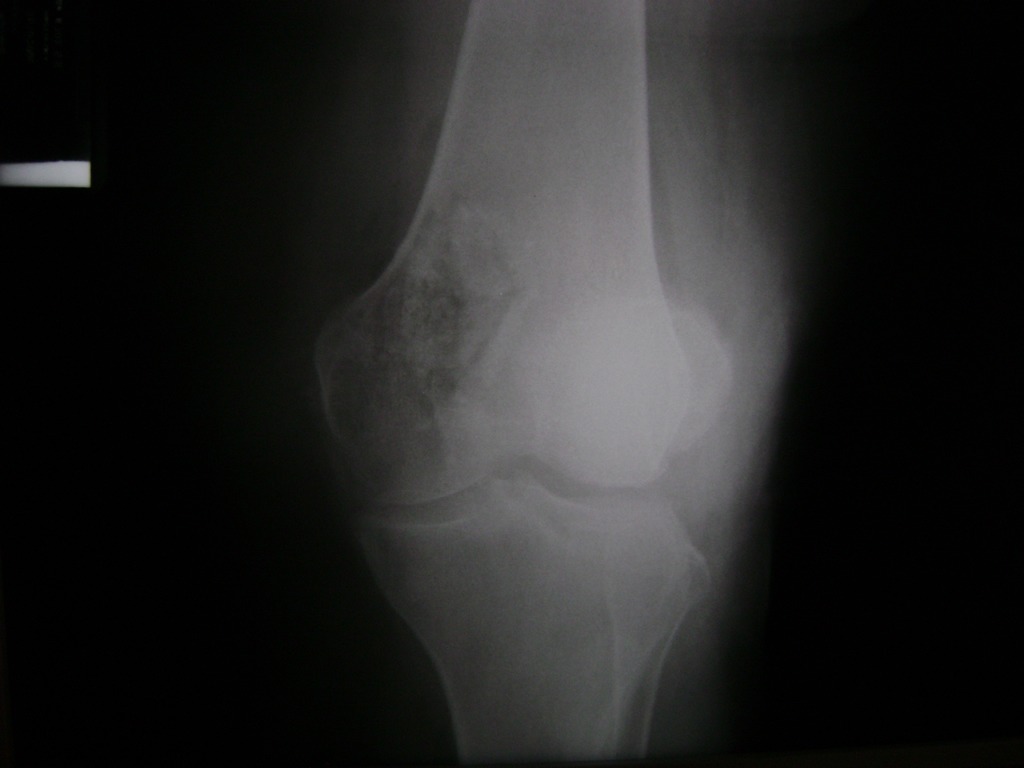

Húmero - Rodilla